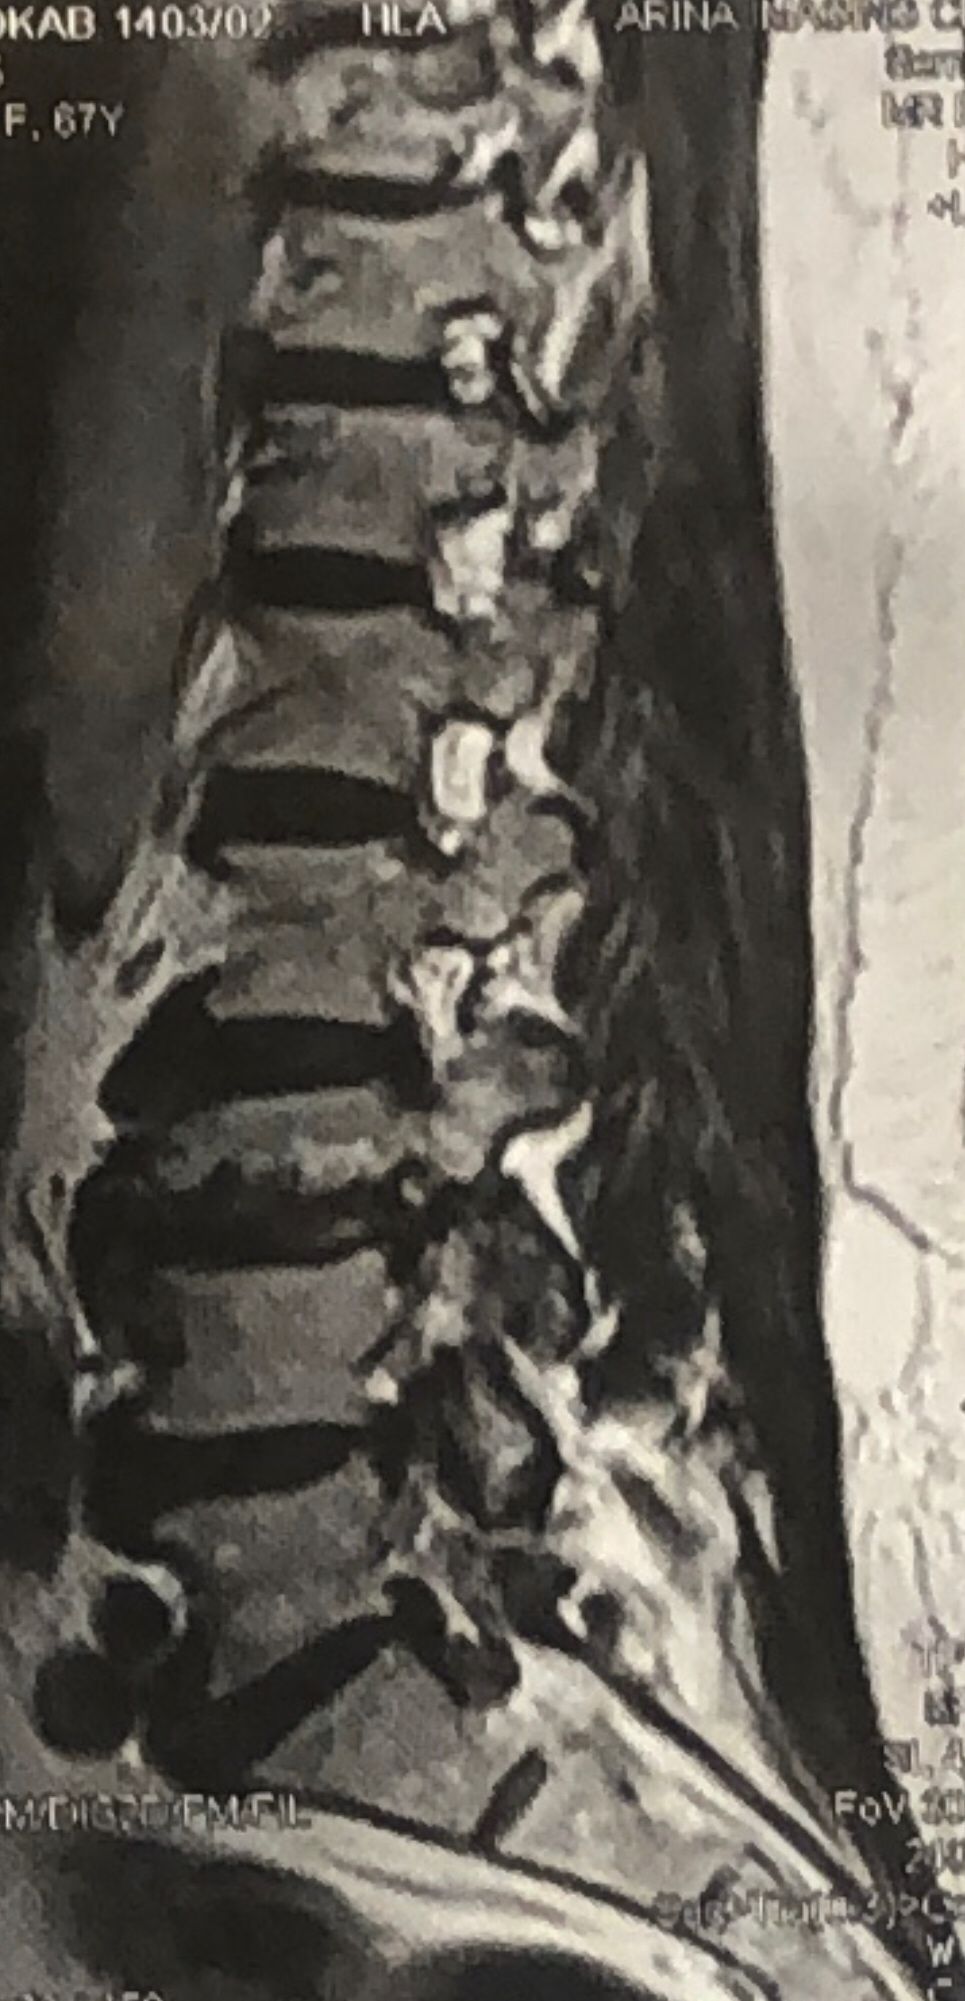

70 yrs old female presented to my clinic today (Oct 06/2024)due to severe LBP with both legs pain for several years.

7 years ago came to my clinic with L leg radicular pain and I referred her to a neurosurgeon. Patient underwent full laminectomy from L1 to S1. Few months after surgery her LBP and legs pain were started and hasn’t improved since then. Now walking aggravates the pain and forces her to bend forward. Patient had mri from 6 months ago. Her mri 7 years ago was similar to the recent mri, just laminectomy and soft tissue collection has been added. In neurological examination p.tvdid not have any neurological deficits. I ordered lower limbs emg/ncv, dynamic lumbar spine X.ray. As a chiropractic Doctor what would be your plan of management for this patient?